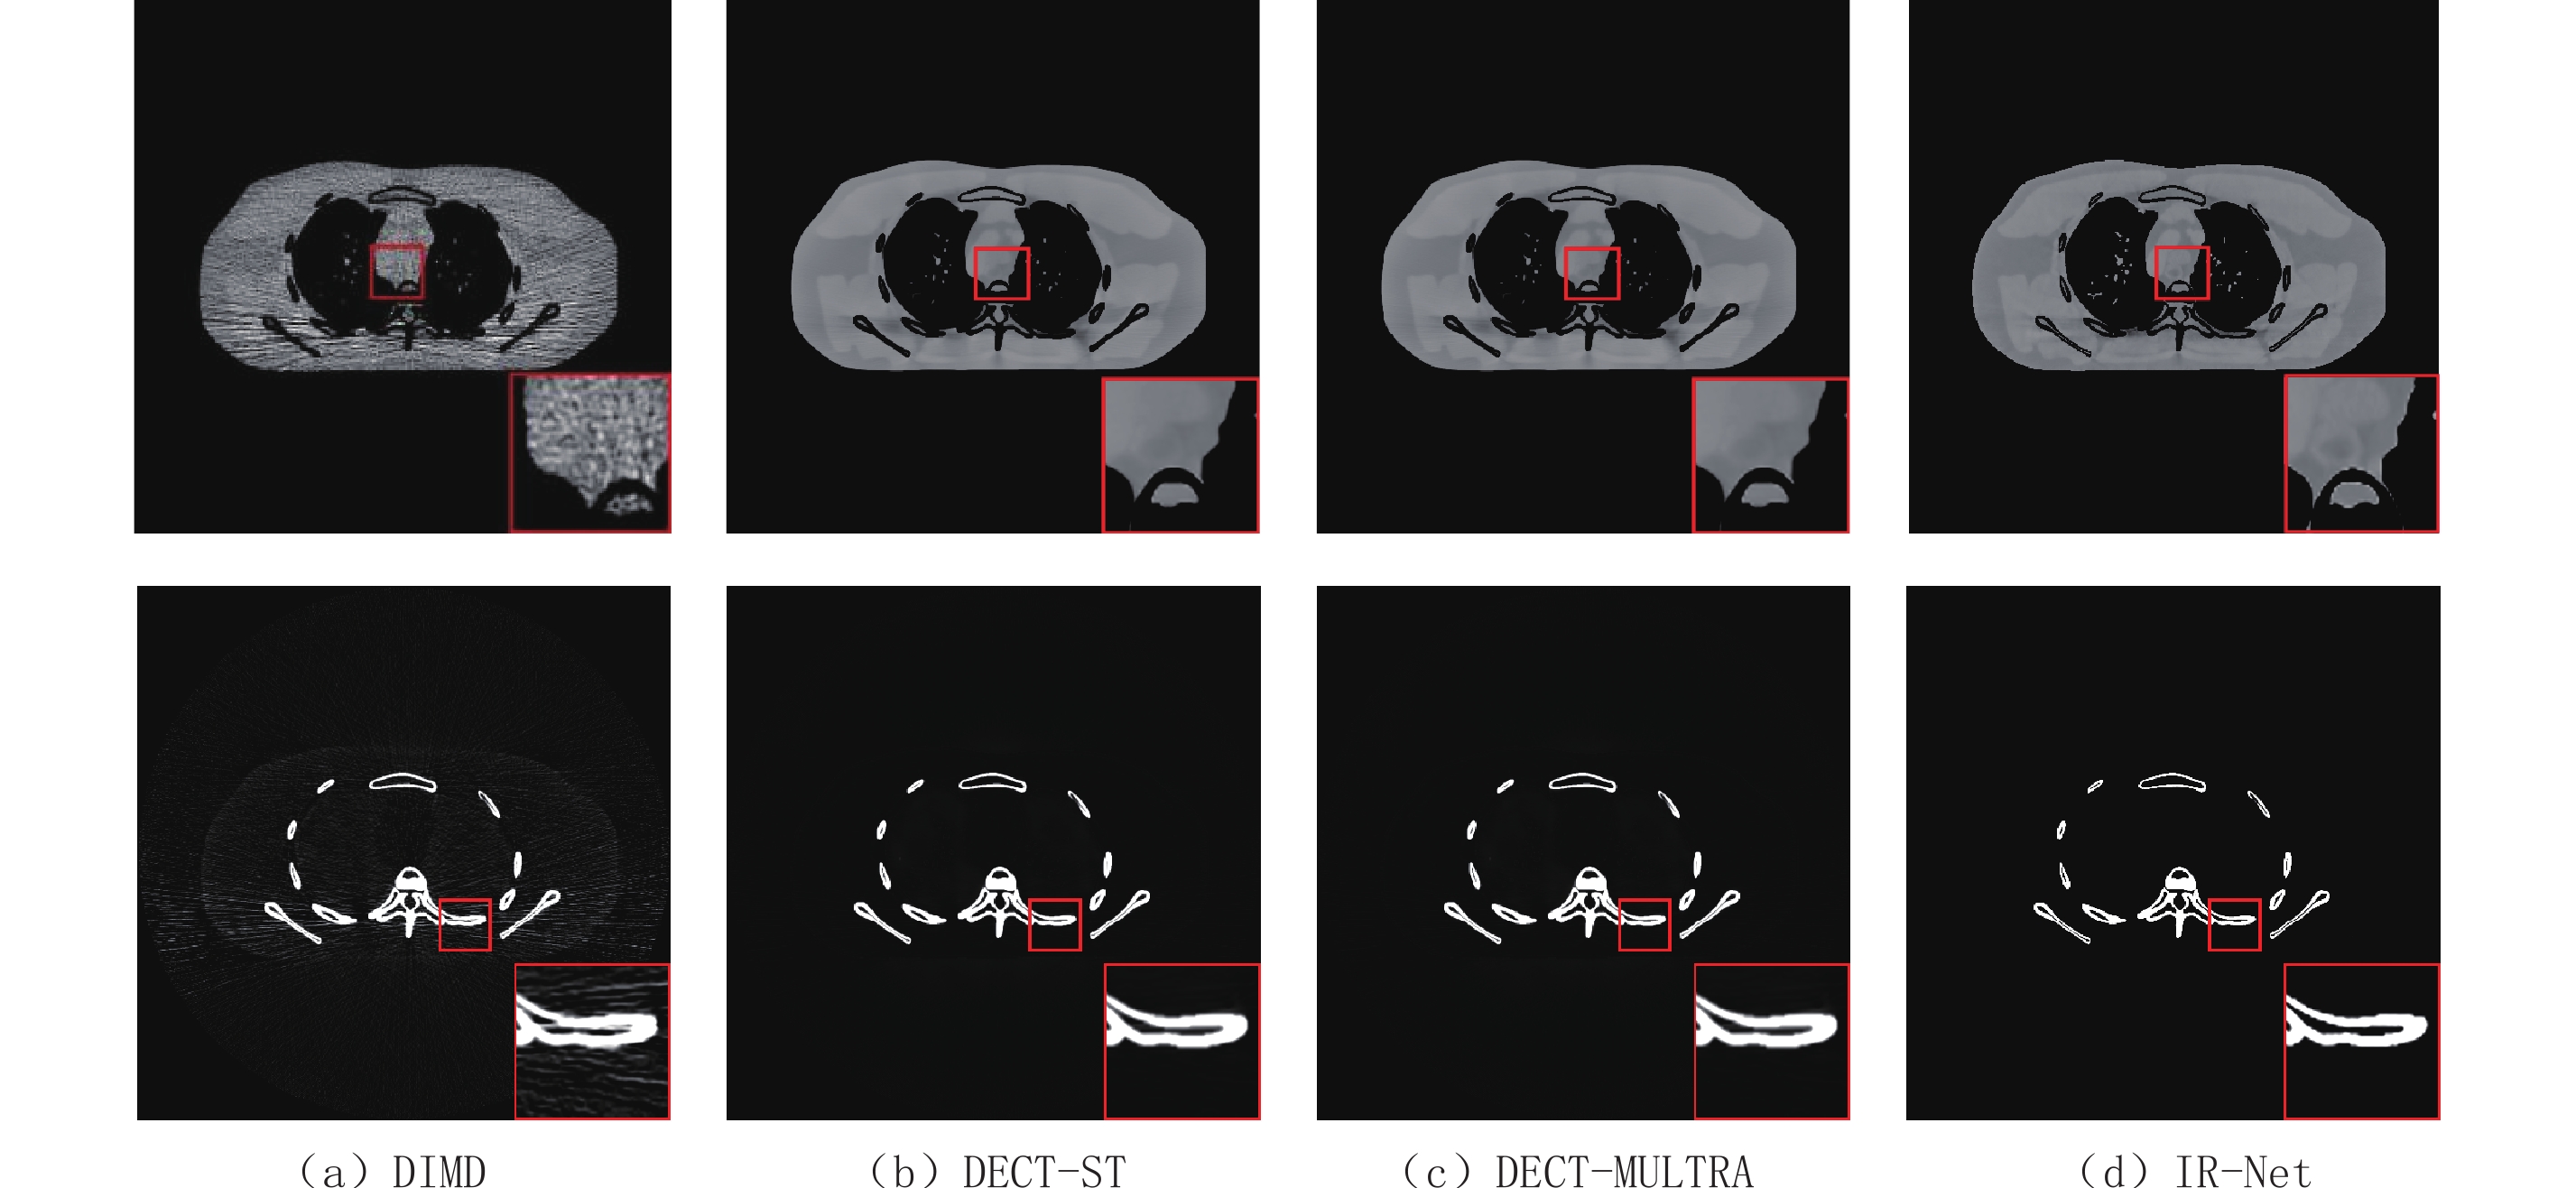

图3为不同算法下的两种基材料分解结果,水和骨的显示窗口分别为[0.7 1.3] g/cm-3和[0 0.8] g/cm-3。由图3可知,DIMD分解得到的基图像含有大量噪声,不能显示任何有用的诊断信息,其他3种方法均能有效抑制噪声和伪影。相比于DIMD,DECT-ST、DECT-MULTRA和本文方法抑制了大量的噪声,且图像清晰,边缘完整。但是由于过度平滑,软组织细节放大处可以观察到DECT-MULTRA模糊掉组织的一些细节信息。此外,DECT-MULTRA和DECT-ST需要以DECT-EP迭代500次的结果作初始基图像,调节参数繁琐,运行时间超过1 h,而本文方法运行测试图像只需要7 s。

为了进一步评价所提方法的优点,图4显示了分解结果偏差的绝对值,提供了视觉上的噪声抑制性能比较,每种基材料的显示窗口为[0 0.3] g/cm-3。通过对比可知,本文方法对分解结果的偏差最小。总的来说,IR-Net网络避免了繁琐的参数调节,提高了材料分解精度,保持了图像边缘清晰。

为了定量评价IR-Net网络在材料分解中的性能,分别计算每种方法下基图像的RMSE、PSNR和SSIM,其结果如表1。由表1知,DIMD获得的两种基材料图像的RMSE值很大,PSNR和SSIM值都很小,说明DIMD材料分解精度最低。与DIMD、DECT-ST和DECT-MULTRA各图像指标相比,IR-Net网络骨和水的基图像的RMSE值最小,说明IR-Net网络分解精度最高;SSIM值最大,证明IR-Net网络分解后的基图像在所有对比算法中与理想图像最相似;此外,其PSNR值均较大,可知IR-Net网络去噪效果好。通过定量综合分析知,IR-Net网络优于其他3种算法,在保持细微结构的同时,能更有效的抑制图像噪声。